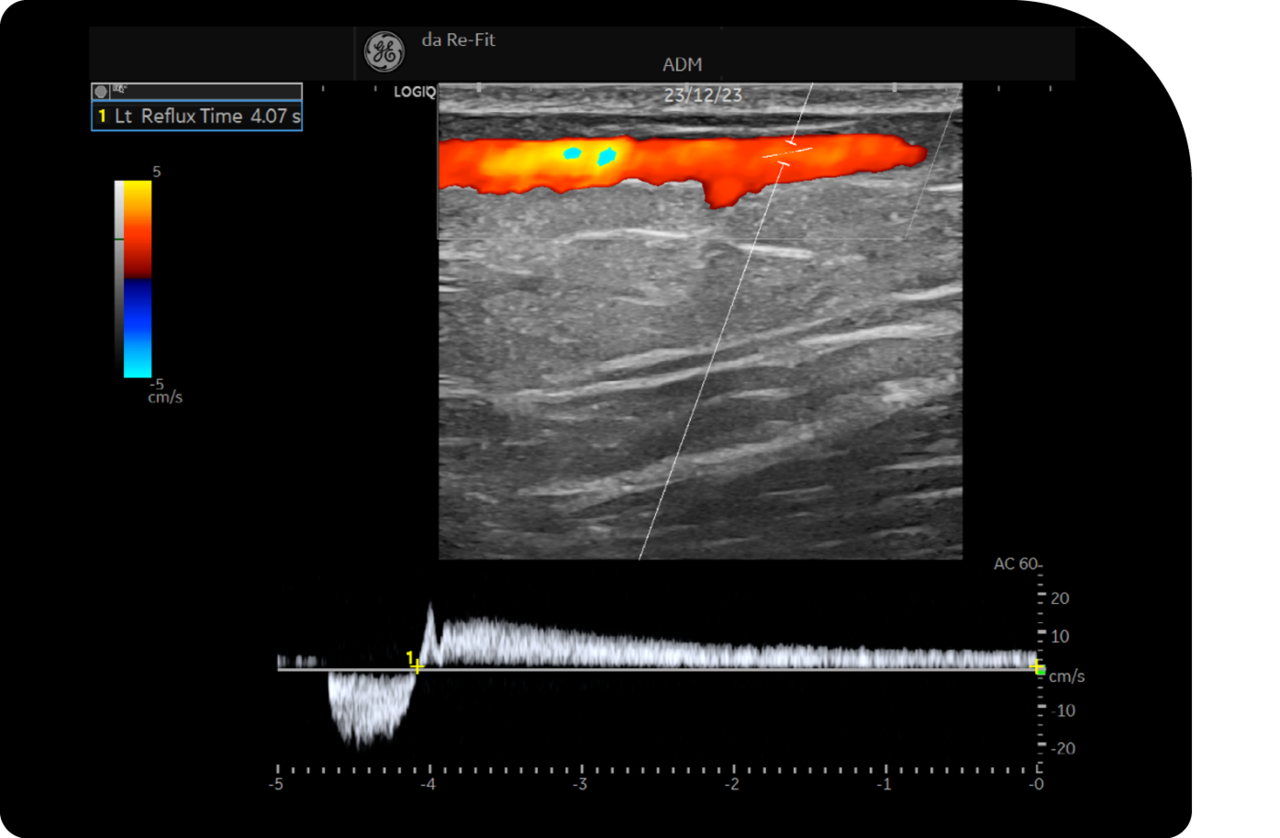

도플러 초음파 정밀 검사

초음파 정밀 검사를 통해 다리의 상태를 실시간으로 확인하여

혈관의 확장 정도, 혈액의 역류 상태 등을 정확하게 진단합니다.

검사 결과를 바탕으로 하지정맥류의 심각도를 판단하고

이를 통해 최적의 수술 또는 치료 방법을 결정합니다.